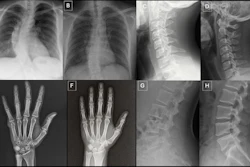

AI algorithms that flag abnormal chest x-rays for immediate review have been widely proposed as a scalable solution, but rigorous prospective evidence has been lacking, they noted. To that end, the researchers launched the LungIMPACT study and tested whether immediate AI prioritization (using qXR version 4.0, Qure.ai Technologies) influenced time to computed CT and lung cancer diagnosis.